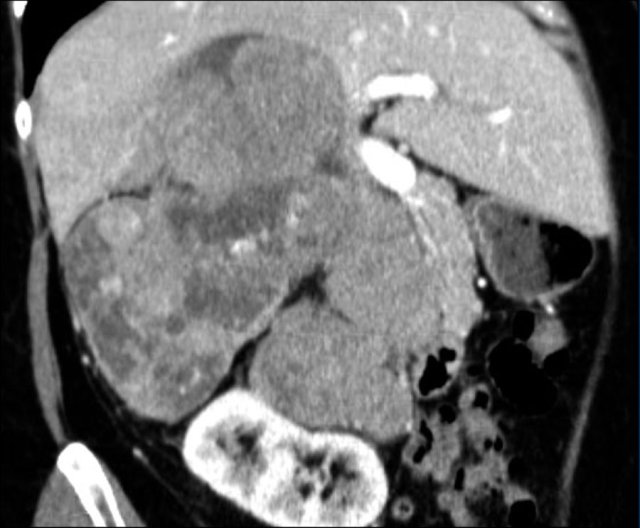

Here a typical example of an adrenocortical carcinoma.

The tumor is bulky and shows heterogeneous enhancement.

Note the 'stellar' central hypodensity.

There is capsular enhancement.

Small adrenocortical carcinomas have less typical features, but also enhance inhomogeneously.

Also note the dystrophic calcifications and areas of necrosis (red arrows).